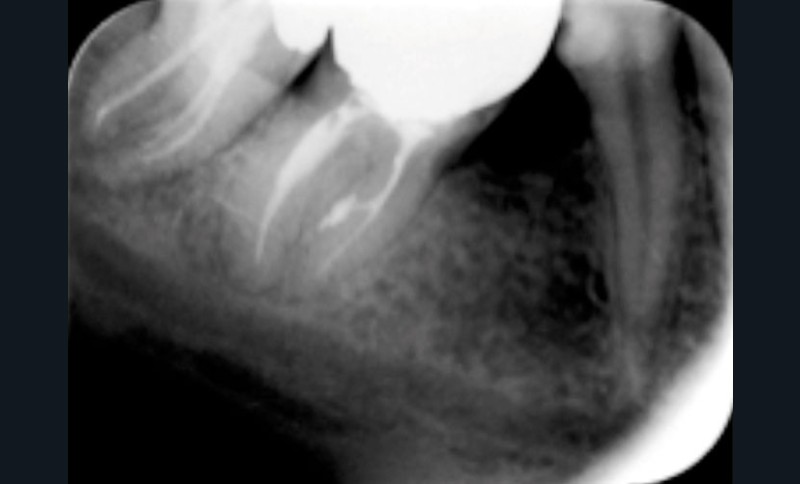

Anatomiquement parlant, les voies de communications entre l’endodonte et le parodonte seront constituées par des canaux radiculaires, qu’ils soient principaux, latéraux, secondaires ou accessoires. Un canal latéral est une ramification du canal principal située dans la région médiane ou coronaire le reliant au ligament alvéolo-dentaire, alors que le canal secondaire est situé dans la région apicale. Le canal accessoire est une ramification du canal secondaire (fig. 1).

Les fêlures et fractures ou les perforations dentaires sont d’autres voies possibles de contamination. Le premier tissu parodontal atteint au contact de la racine sera le desmodonte. La diffusion de l’infection suivra la voie du sulcus gingival ou celle osseuse alvéolaire.

Lorsqu’un patient se présente en consultation avec une lésion au contact d’une dent (fig. 2), le praticien doit suivre une démarche diagnostique afin de recueillir le maximum d’informations sur la situation clinique :